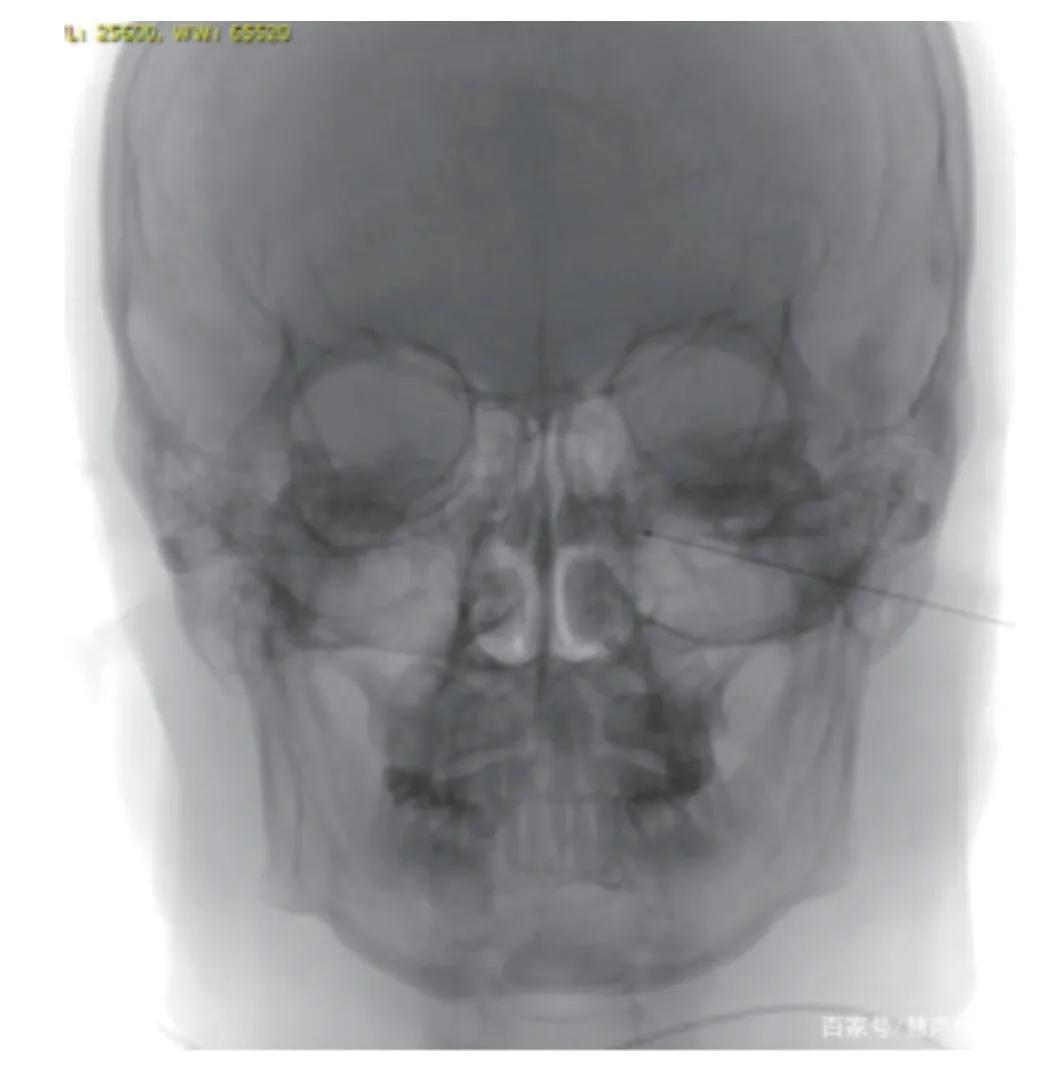

传统的治疗方法主要是通过药物治疗改善不适症状,但这是治表不治本,往往是治了便好,好了又犯,还会越犯越重。也有行副交感神经切断术治疗过敏性鼻炎,但副作用太多,使用较少。最新研究表明,蝶腭神经节是中枢神经通过自主神经调节鼻腔血管和腺体的总枢纽,使用脉冲射频对蝶腭神经节进行调控,可以使自主神经重新恢复平衡功能,改善过敏性鼻炎各种不适症状。

蝶腭神经节脉冲射频调控术治疗过敏性鼻炎,起效快、疗效显著,且具有安全性及精准性,有大量患者通过这个微创手术,解除了鼻炎的困扰,恢复了正常的生活。希望这种方法能够让更多的人看到,更多的人受益。